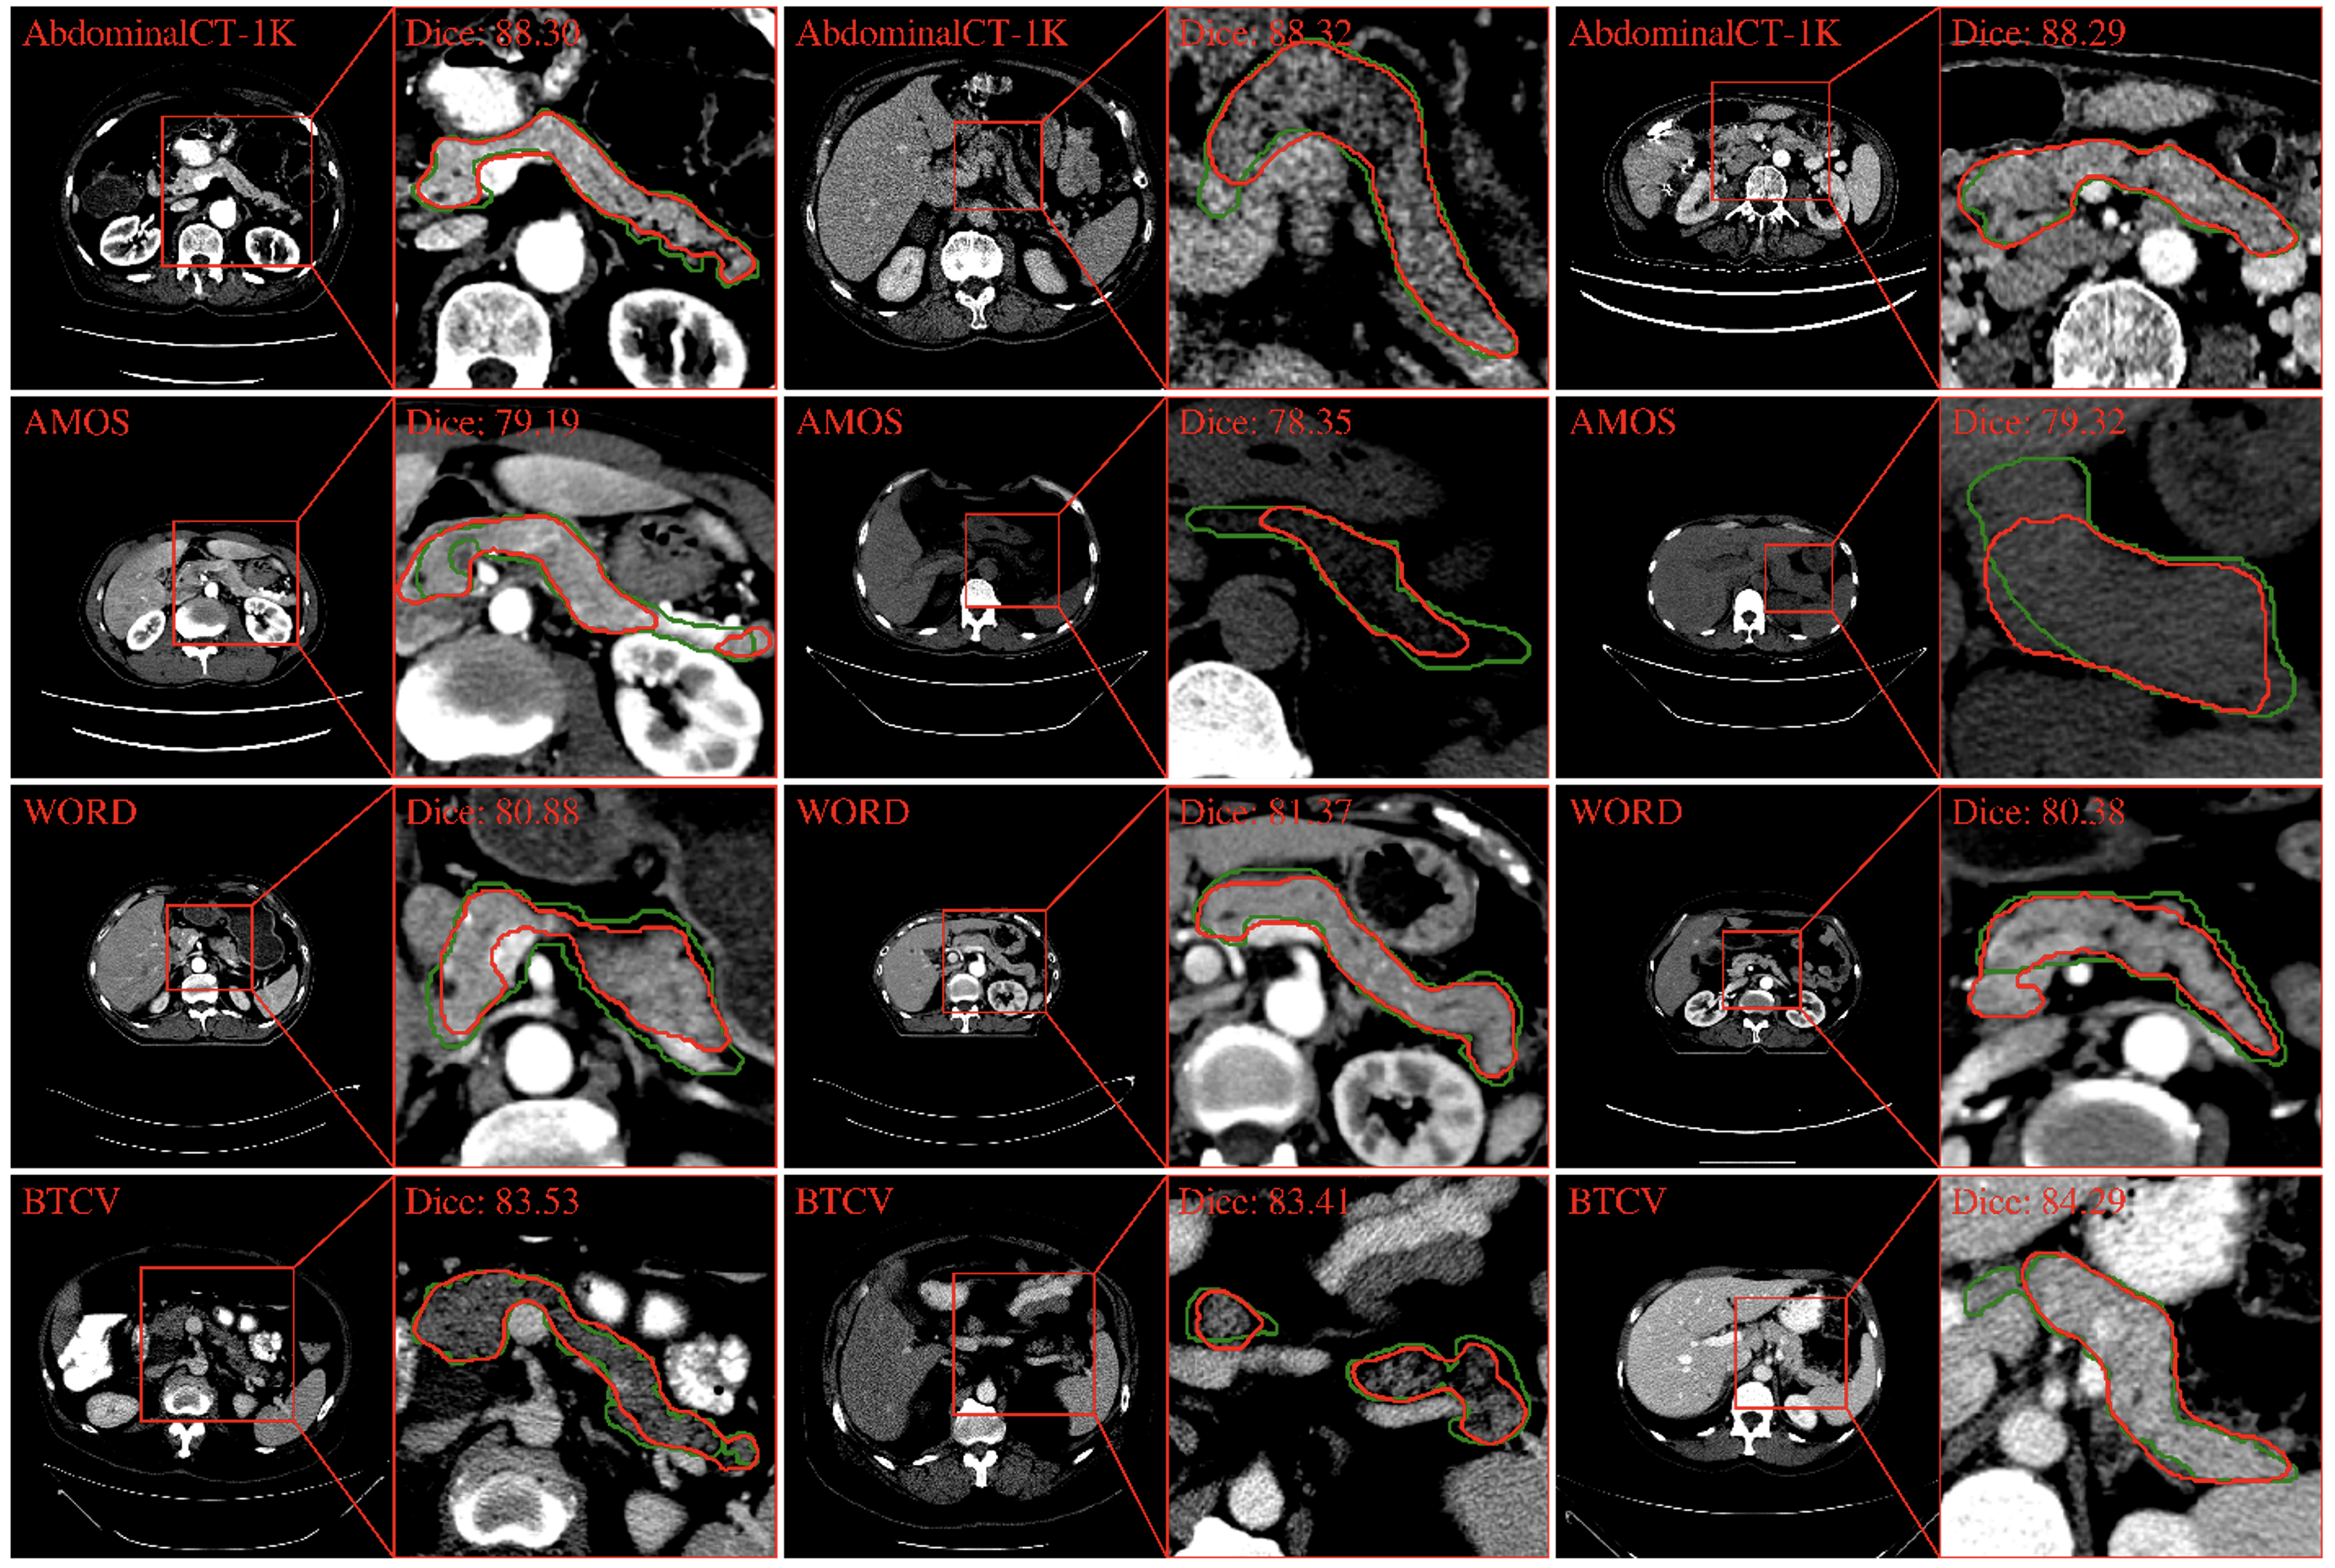

4.2 Segmentation performance with CT scans

In the AbdomenCT-1K dataset, PanSegNet yielded an average Dice score of 88.31% with a standard deviation of 7.24% (median: 89.64%) and an HD95 distance of 5.10 mm with a standard deviation of 8.43 mm (median: 3.16 mm) (Table 4). Visual examination of the segmentation results, as depicted in Figure 4, demonstrates the model’s accuracy in delineating the intricate contours of the pancreas, closely aligning with the ground truth annotations. Segmentation performance dropped when our trained model was applied directly to AMOS, WORD, and BTCV external datasets. These datasets represent real-world clinical scenarios and potentially differ in distribution from the AbdomenCT-1K training data (domain shift). As expected, the model’s performance drops on these datasets, indicating the limitations of directly applying models trained on specific datasets to more diverse real-world settings. Specifically, the Dice coefficients decreased to 78.79% (-10.78%, p-value: 2×10-32), 80.89% (-8.40%, 6.13×10-25), and 83.71% (-5.21%, p-value: 6.05×10-4), respectively. These statistically significant decreases highlight the importance of addressing domain shift challenges when deploying models in real-world clinical applications. It is worth to note that despite the domain-shift challenges, PanSegNet obtains highly promising dice scores.

Refer to caption

Fig. 4: Segmentation results for CT pancreas across multiple datasets (green indicates the predicted pancreas, and red indicates the annotations). While AbdominalCT-1K exhibits robust segmentation performance, marked by precise boundary delineation, a domain shift is observed when extending the model to the AMOS, WORD, and BTCV datasets, underscoring the significance of addressing domain shifts for clinical applications. For a fair comparison, we select the visualization samples near the median value according to the Dice coefficient distribution (note: Dice is calculated volumetrically).